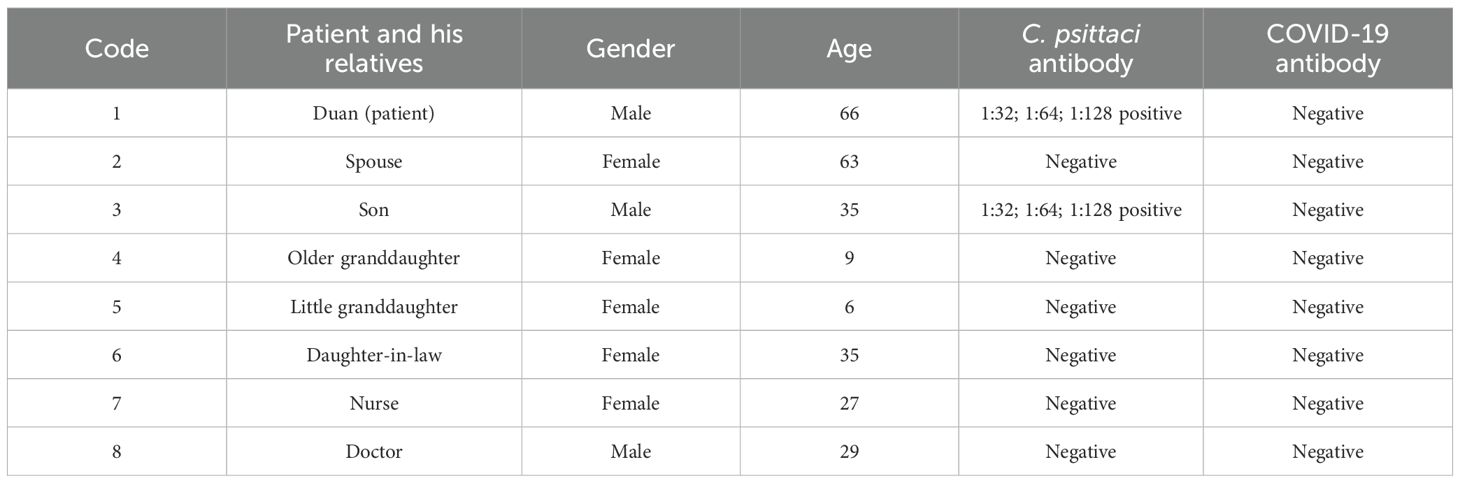

For C. psittaci-specific antibodies, IgG antibody titers were arranged from 1:64 dilution on December 25 and increased to 1:128 dilution on December 27, 2019, in a time-course manner (Figure 4). Compared to the patient’s sera, IgG titers were from 1:32 to 1:64 to 1:128, and the serum samples from other close contacts were negative in the test. Meanwhile, antibodies against COVID-19 were negative (Table 2). Serum samples from the patient were also tested for antibodies against common respiratory pathogens, including influenza A/B virus, respiratory syncytial virus, C. pneumoniae, and M. pneumoniae. All results were negative.

Table 2. Detection of Chlamydia psittaci-specific IgG and COVID-19 antibodies in the sera of the patient and his close contacts.